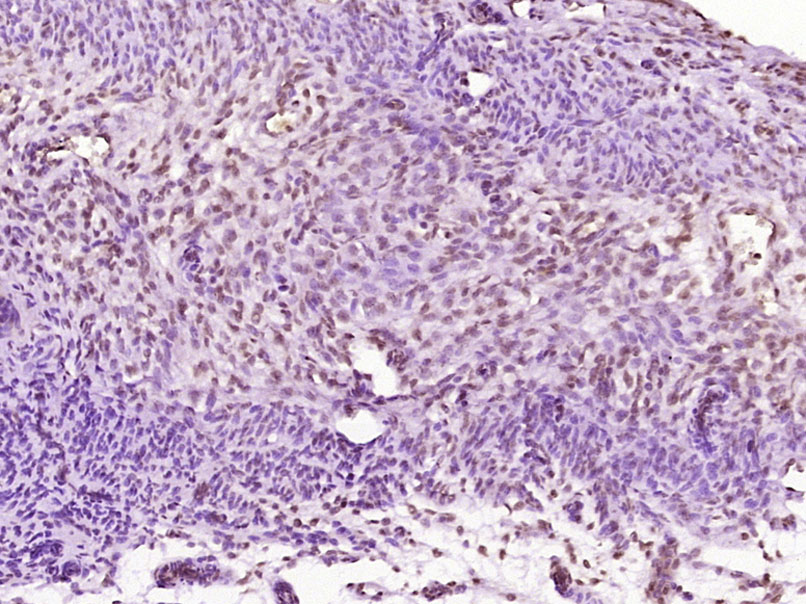

| 产品应用 | WB=1:500-2000, IHC-P=1:100-500, IHC-F=1:100-500, IF=1:100-500 Not yet tested in other applications. |

| {IHC-P} | {1:100-500} |

[IF={{ 1 }}] {Han, Chunlong. et al.Peroxisome Proliferator-Activated Receptor Gamma Coactivator-1-Alpha in Endometriosis: Expression, Regulation, and Potential Role.CUREUS JOURNAL OF MEDICAL SCIENCE.2025 Jan 12;17(1):e77341.} {IHC} {Human}